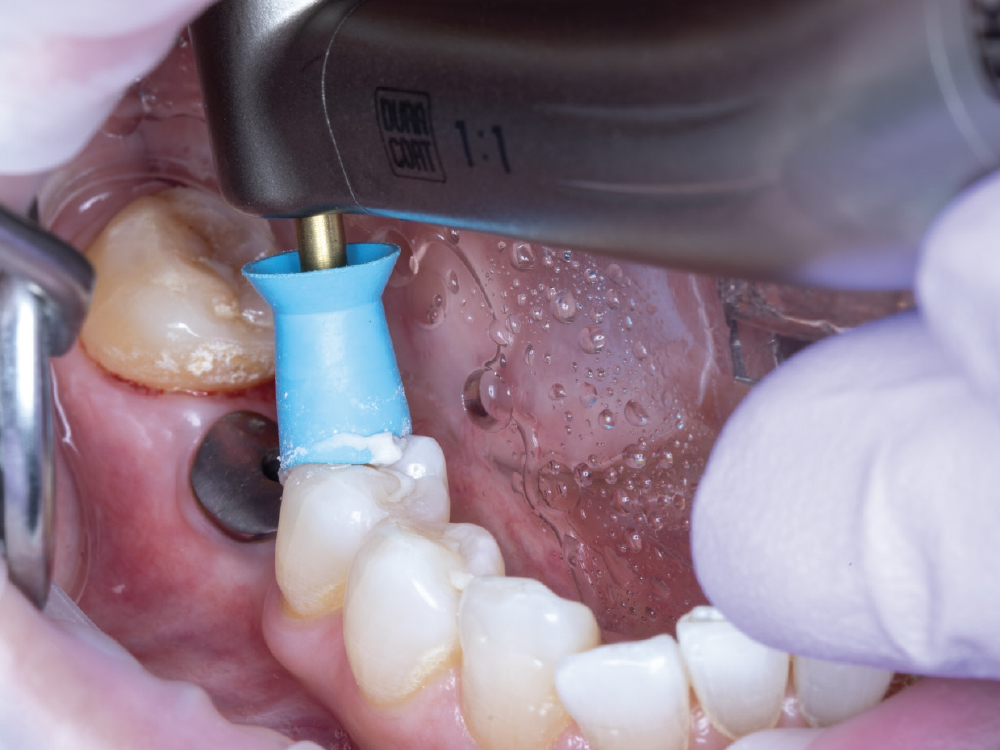

Verify Complete Scan Body Seating

Verify Complete Scan Body Seating. Confirm the scan body is fully seated to the implant before scanning — how it seats is precisely how the final restoration will seat. Use a radiograph if there is any question about complete seating, as an incompletely seated scan body will result in a restoration that does not fit, regardless of scan quality. Apply firm finger pressure or use a seating instrument, then verify there is no rocking or movement. Check for any tissue interference preventing complete seating and address it before scanning.

Thoroughly Scan the Scan Body Geometry

Thoroughly Scan the Scan Body Geometry. Complete, high-resolution capture of the scan body is non-negotiable. This is how laboratory software determines the precise three-dimensional position and angulation of the implant. The software matches the scanned scan body with its library file to establish the implant location in space. Scan from multiple angles to ensure all identifying features and surfaces are captured, as incomplete scan body data leads to misaligned restorations regardless of how perfect the rest of the scan appears. Verify that all reference markers, grooves, or geometric features are clearly visible in the acquired scan.

Capture the Surrounding Soft Tissue Immediately

Capture the Surrounding Soft Tissue Immediately. Scan the peri-implant soft-tissue architecture as soon as the scan body is placed, before the tissue collapse occurs. Gingival tissues begin to collapse and distort within minutes of scan body insertion, and the initial tissue contours are critical for creating proper emergence profiles. Work efficiently but thoroughly to document the tissue topography in its most accurate state.